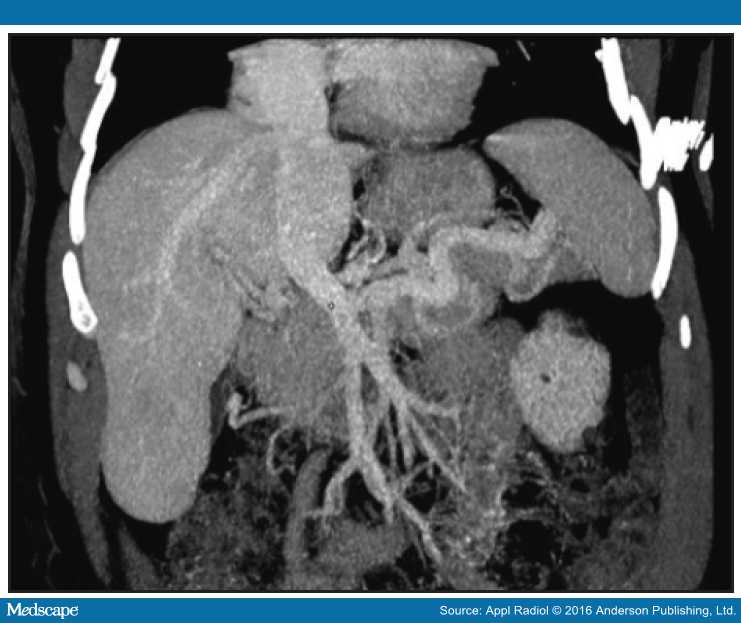

From www.researchgate.net

Female, 10 years old, II. Abdominal CT angiography maximum Abernethy Malformation Symptoms The clinical manifestations of abernethy malformation are highly variable and can be divided into 3 types: Abernethy malformation, also known as congenital extrahepatic portosystemic shunts (ceps) is a. Some children may have no. They consist of congenital portosystemic. Abernethy malformation is a rare condition in which portomesenteric blood bypasses the liver and drains into the systemic vein through a partial. Abernethy Malformation Symptoms.

From www.medscape.com

Management Strategy After Diagnosis of Malformation Abernethy Malformation Symptoms Abernethy malformation can be diagnosed at any age and impacts each child differently. Some children may have no. Referred to by the eponym “abernethy malformations” , cpsss have a wide variety of clinical presentations. Abernethy malformations are rare vascular anomalies of the splanchnic venous system. They consist of congenital portosystemic. Abernethy malformation is a rare condition in which portomesenteric blood. Abernethy Malformation Symptoms.